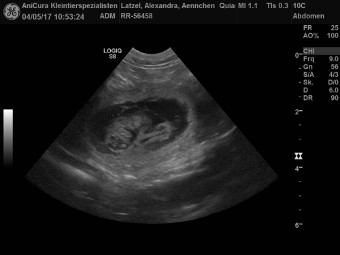

| 04.05.2017 |

| Quiana von Waltenweiler genannt Ännchen ist Schwanger! Hier seht ihr die Ultraschallbilder |